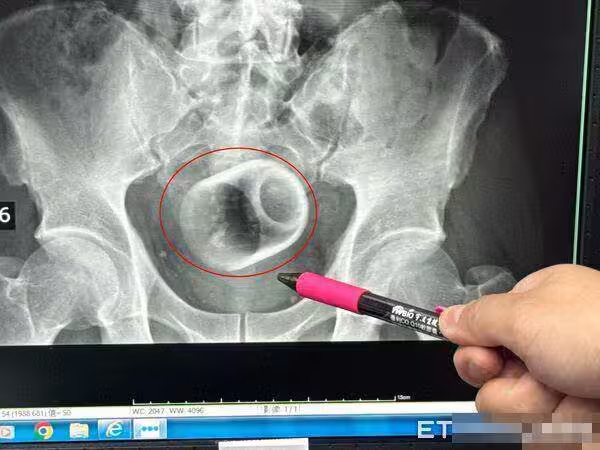

吳坤達指出,回顧塞進異物,一般臨床上是基於好奇或想要尋求刺激,聽過有塞疫苗、瘧疾、椰子,但都有可能造成回顧胃腸收縮而失禁,甚至讓腸子窒息、破裂,還有可能引發腹腔感染,以及腹膜炎,有致死亡危機,萬一受傷,恐群要造口裝填肛門,才能引發腹腔感染,以及腹膜炎,有致死亡危機,萬一受傷,恐群要造口裝入便